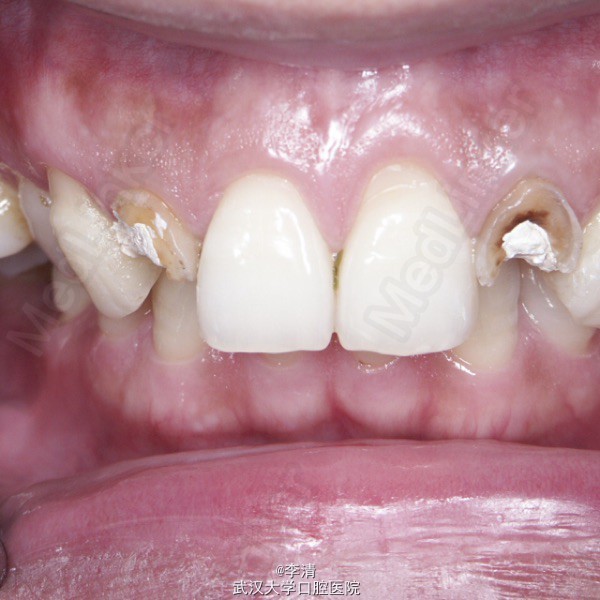

残根 残根

方某,36岁,男,上侧切牙在外院行冠修复,近期该牙疼痛,拆除原义齿,并行牙髓治疗两周。要求美容修复该牙

查体 辅查

X片示侧切牙行根管治疗,根尖无明显暗影

诊断 处理

侧切牙残根 行纤维桩,铝瓷全瓷冠修复